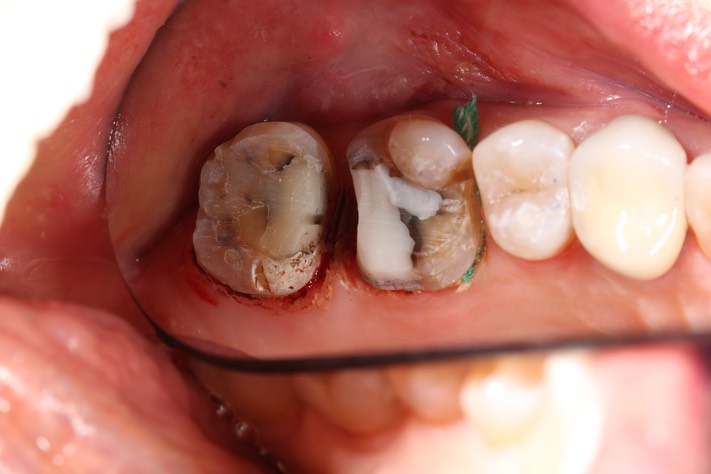

Gary Umeda #14-15 prep

Gary Umeda #14-15 prep 2